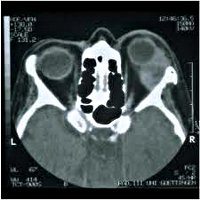

Удаление кранио-орбитальных опухолей. Иссечение новообразований, расположенных в орбитальной области и прилегающих областях. Основным принципом удаления новообразований черепа, растущих в полости орбиты, или опухолей орбиты, прорастающих в полость черепа, является радикализм иссечения патологического очага, сохраняющий глаз и его функции. Степень вмешательства зависит от размера, характера и места новообразования. В некоторых случаях костная пластика необходима после удаления опухоли. При злокачественных процессах полное удаление кранио-орбитальной опухоли часто невозможно, операция дополняется лучевой терапией и приемом химиотерапевтических препаратов.

Поскольку доброкачественные опухоли краниоорбитальной локализации (например, менингиома зрительного нерва) могут сдавливать зрительный нерв, орбитальные структуры и области мозга, прилегающие к костям основания черепа, даже при небольших размерах, операция показана, когда они найдены. В некоторых случаях, например, при медленных темпах роста неоплазии в клинической неврологии, используется тактика ожидания и динамический мониторинг пациента до появления первых клинических признаков опухолевого процесса. Злокачественные новообразования краниоорбитальной области при отсутствии противопоказаний подлежат удалению.

Лимфоидные опухоли, обширные кранио-орбитальные новообразования, прорастающие ткани головного мозга с участием пирамиды височной кости и кавернозного синуса, а также новообразования с множественными метастазами не удаляются. В качестве общего противопоказания рассматриваются тяжелое состояние пациента, декомпенсированная соматическая патология, острые инфекции и нарушения свертываемости крови.